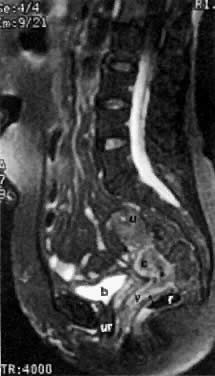

Diagnosis of cervical carcinoma is usually made by history, physical examination, Pap smear, and in certain cases, dilatation and curettage. Radiology plays a complementary role in the more difficult cases. On MRI7 and other cross-sectional imaging techniques, the cervix is usually normal in appearance in early cervical cancer. Locally confined cancer appears as a focal mass of medium signal intensity, which either distends the endocervical canal or focally disrupts the normal low-signal-intensity cervical stroma on T2-weighted MRI (Fig. 4A).

Fig. 4. A. Sagittal T2-weighted MRI of the pelvis shows increase in size and signal intensity of the cervix (proven cervical carcinoma). B. Sagittal T2-weighted MRI of the pelvis shows resolution of the tumor after radiation therapy. ( u, uterus; c, cervix; v, vagina; b, bladder; r, rectum; e, endometrium; arrow, uterine junctional zone.)

The presence of hydrometras should raise the suspicion of cervical or endometrial carcinoma. It is best demonstrated by ultrasound (see Fig. 6A), but can be seen by both MRI (Fig. 7) and CT (Fig. 8).11,12 This finding, however, is nonspecific because it can also be seen in benign cervical strictures caused by either previous cervical inflammation (Fig. 9) or pelvic irradiation (Fig. 10).

Fig. 7. T2-weighted sagittal MRI of the pelvis shows cervical carcinoma ( c) causing hydrometras ( h ).

Fig. 8. Axial CT scan of the pelvis in a 55-year-old woman with stage IB cervical carcinoma causing obstruction of the uterus ( u ). ( b, bladder; arrows, uterus; r, rectum.)

Fig. 9. Sagittal scan of the uterus ( u) shows hydrometras. Cervix ( c) is normal in size. Patient had no known cervical or endometrial cancer.

Fig. 10. Sagittal T2-weighted MRI of the pelvis shows moderate hydrometras ( h) caused by postirradiation cervical scarring.